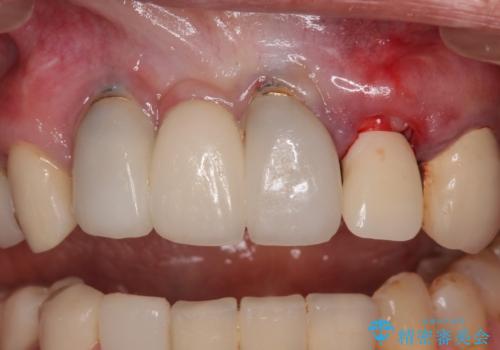

- 以前から頻繁に前歯が土台から外れてしまうことがあり、インプラントによる治療を希望して来院された患者様です。

歯根が割れていることはありませんでしたが、残っている歯質が全て歯肉よりも深い位置にあるため、土台としての機能は不足している状態でした。

歯根周辺の骨や歯肉の状態は良く、抜歯して速やかにインプラントを埋入し、即日で仮歯を装着するプランにて治療を行うこととしました。

初回カウンセリング時にはセラミッククラウンが装着されていましたが、インプラント治療でのご来院時には前歯は外れて紛失をしてしまったとのことでした。